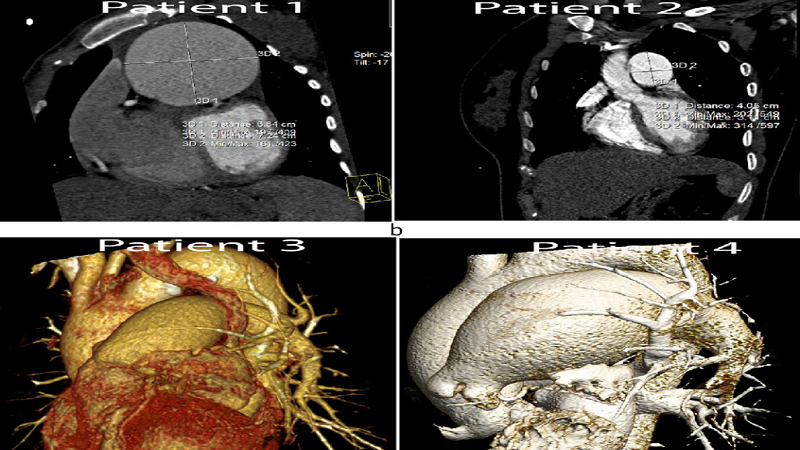

Sự ra đời của kỹ thuật chụp cắt lớp 128 dãy là một bước tiến dài trong lĩnh vực chẩn đoán và điều trị bệnh lý tim mạch. Phương pháp này không chỉ nhận diện nhanh những bất thường trong cấu trúc của tim và hệ mạch mà còn có thể đánh giá tốt chức năng hoạt động của chúng. Từ đó giúp phát hiện sớm bệnh, can thiệp kịp thời để giảm thiểu những rủi ro có thể xảy ra.

So với các loại xét nghiệm hình ảnh thông thường như chụp X-quang, chụp CT truyền thống thì hình ảnh chụp CT 128 dãy sắc nét hơn nhiều vì bộ phận kiểm tra được mô phỏng theo không gian ba chiều. Đặc biệt, chúng tạo ra hơn 100 lát cắt nên cho hình ảnh vừa bao quát lại vừa chi tiết. Do đó khi nhìn vào kết quả, bác sĩ có thể nhận diện ngay những bất thường nếu có, từ đó giúp hỗ trợ tích cực vào việc chẩn đoán chính xác bệnh và rút ngắn thời gian thăm khám của bệnh nhân.